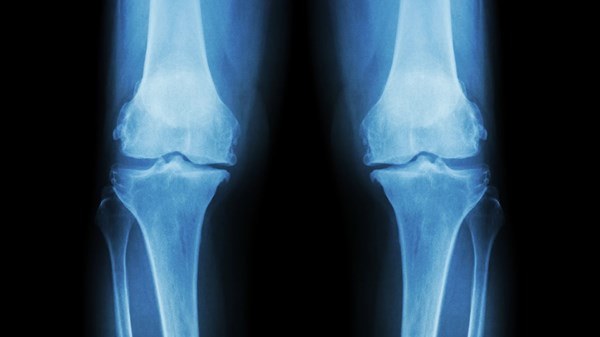

طوّر باحثون من جامعة سري البريطانية (University of Surrey) نظام ذكاء اصطناعي جديداً قادراً على توقّع شكل الأشعة السينية لركبة المريض بعد عام كامل، في خطوة قد تُحدث تحولاً في فهم وتشخيص وإدارة مرض الفُصال العظمي (Osteoarthritis)، أحد أكثر أمراض المفاصل شيوعاً في العالم.

وأوضح الباحثون أن التقنية الجديدة تستخدم خوارزميات تعلم آلي متقدمة لتوليد صورة مستقبلية واقعية للركبة ومؤشر خطر يقدّر احتمالية تقدم المرض، ما يمنح الأطباء والمرضى تصوراً بصرياً دقيقاً لمسار الحالة بمرور الوقت.

وتم تدريب النظام على قرابة 50 ألف صورة أشعة سينية للركبة مأخوذة من نحو 5 آلاف مريض، وأظهر تفوقاً ملحوظاً على أدوات الذكاء الاصطناعي الأخرى في التنبؤ بتطور المرض، إذ يعمل بسرعة أكبر بتسع مرات تقريباً وبكفاءة أعلى.

يستخدم النظام نموذجاً توليدياً متقدماً يُعرف باسم نموذج الانتشار (Diffusion Model) لتوليد نسخة مستقبلية من صورة الركبة، مع تحديد 16 نقطة أساسية في المفصل تمثل المناطق التي يراقبها الذكاء الاصطناعي بحثاً عن تغيّرات، بهدف تعزيز الشفافية ودعم التفسير السريري.